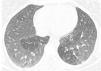

Un varón de 61 años de edad, no fumador, con antecedentes de colitis ulcerosa y tratado con sulfasalazina durante más de 3 años acudió a la consulta en enero de 2012 por presentar tos seca y disnea progresiva de 6 meses de evolución. La espirometría reveló una obstrucción grave del flujo aéreo (FEV1=890ml [30%]; FVC=1.670ml [44%]; FEV1/FVC=[53%]). La tomografía computarizada de alta resolución (TACAR) mostró opacidades pulmonares bilaterales con predominio en las áreas pulmonares superiores y la analítica indicó eosinofilia en sangre y en el LBA (7,6g/l y 80%, respectivamente). Al paciente se le diagnosticó de neumonía eosinofílica, tras lo que se suspendió la sulfasalazina y se inició tratamiento con 40mg de prednisona una vez al día, con lo que se observó mejoría clínica y funcional. No se hizo seguimiento del paciente. En septiembre de 2013, el paciente acudió de nuevo a la consulta por presentar tos seca y disnea progresiva de 5 meses de evolución. Había suspendido la prednisona prematuramente y, contrariamente a nuestras recomendaciones, seguía tomando sulfasalazina. La espirometría indicó un defecto ventilatorio de tipo obstructivo (FEV1 = 905ml [31% del valor previsto]; FVC = 1.300ml [34% del valor previsto]; FEV1/FVC=[69% del valor previsto]). La gasometría arterial reveló hipoxemia, la TACAR mostró áreas bilaterales de atenuación en mosaico (fig. 1), y la analítica indicó 1,9g/l de eosinófilos en sangre. En la fibrobroncoscopia se observó hiperemia de toda la mucosa del árbol traqueobronquial, las biopsias endobronquiales mostraron una prominente inflamación eosinofílica, y la fórmula leucocitaria del LBA indicó la presencia de un 32% de eosinófilos. Se suspendió la sulfasalazina y el paciente inició tratamiento para la BOH con 40mg de prednisona una vez al día, y nebulizaciones de broncodilatadores y corticosteroides con una notable mejoría clínica y funcional. En noviembre de 2013, el FEV1 era de 2.900ml (114%) y la FVC de 3.810ml (105%). Se recomendó reducir gradualmente la dosis inicial de corticosteroides durante varias semanas hasta alcanzar la dosis mínima capaz de mantener una función pulmonar normal y controlar la sintomatología. El paciente también recibió formoterol/budesonida.